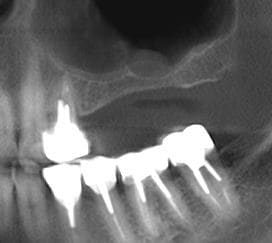

pour illustrer cette utilisation du bioactys, voici un cas (ce matin, mise en focntion des implants à 7 mois post_op)

Pano 7 mois cesxkm - Eugenol